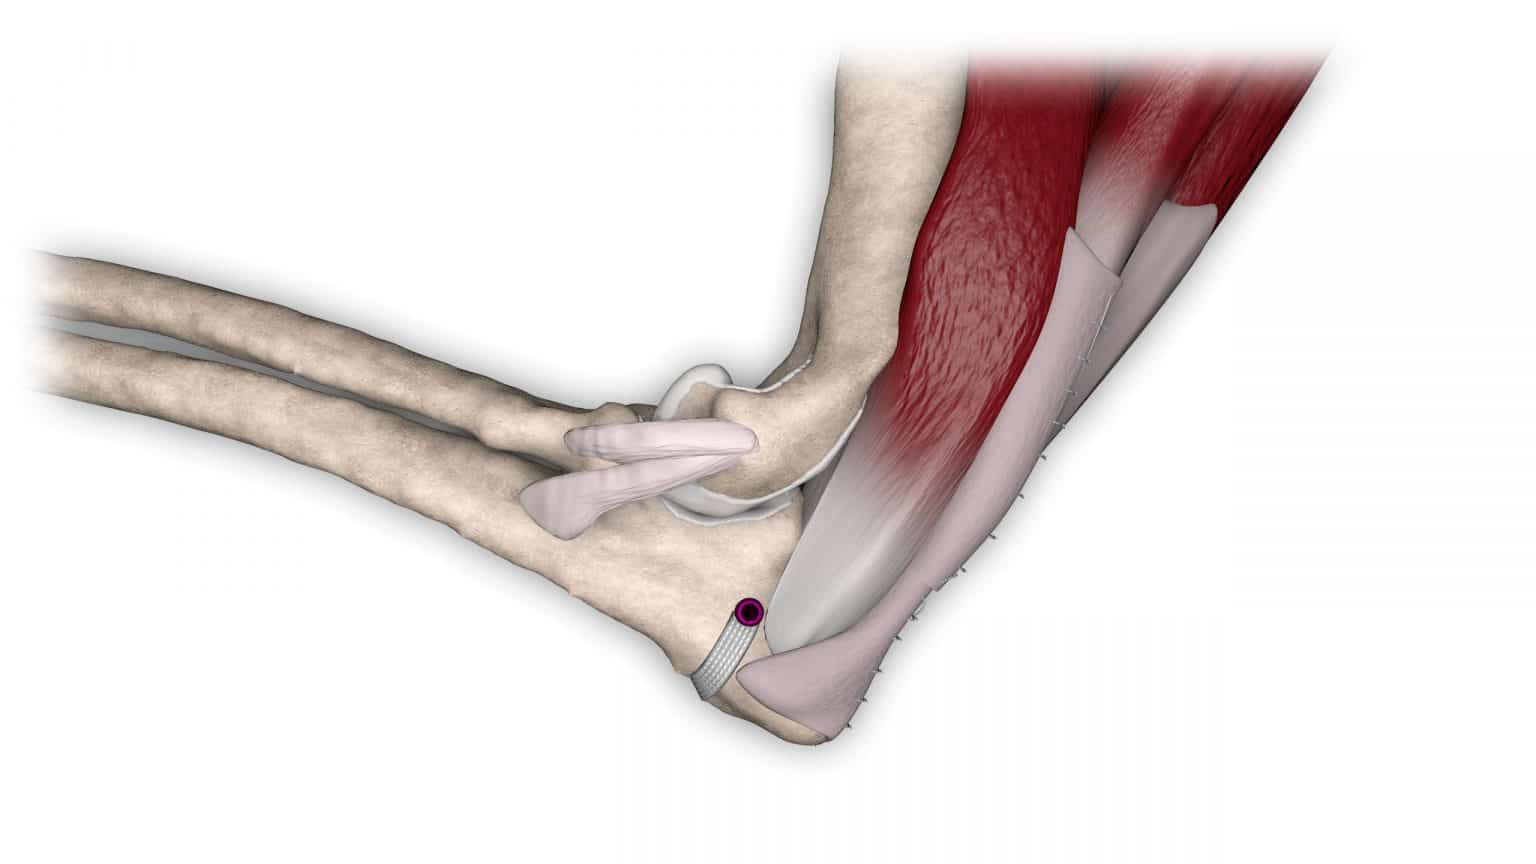

NOVALIG® je syntetický vaz, který lze použít k rekonstrukci vazů a rychlému obnovení jejich fyziologických funkcí.

V případě zkřížených vazů umožňuje intraartikulární rekonstrukci v izometrických bodech připojení, čímž obnovuje biomechaniku kolene a všechny funkce natrženého vazu.

V případě více vazů kolene (kraniální, kaudální, kolaterální) je možné pomocí NOVALIG® anatomicky rekonstruovat každý vaz.